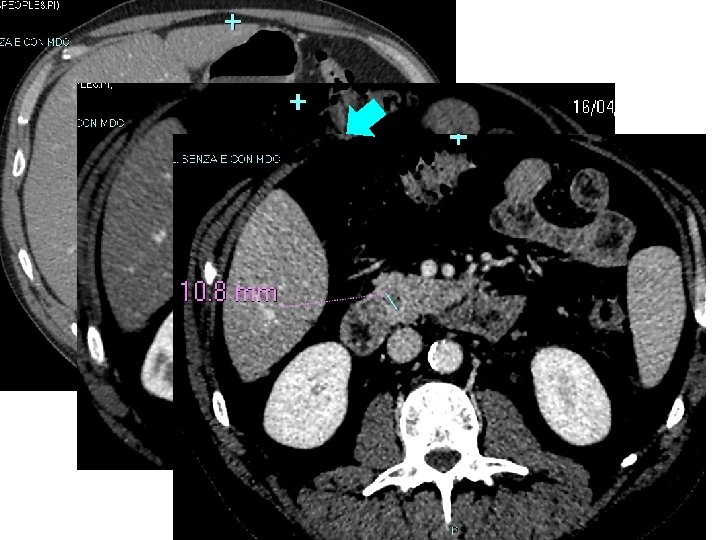

Diagnosi di tumori anche “piccoli” (< 2 cm), grazie ai segni diretti e indiretti Sensibilità per T < 2 cm attorno al 77% Strumento potente nella stadiazione locale e a distanza Monitoraggio dopo Chemio e/o Chirurgia

OBT: diagnosticare tumori “piccoli” segni diretti segni indiretti

Il problema del tumore piccolo • Effetto massa minimo non distinguibile dal resto della ghiandola (non segni diretti) • Ancora non ha dato segni indiretti • Talvolta è vascolarizzato come il restante parenchima (ha la stessa densità alla TAC contrasto della ghiandola normale) ISODENSO • Nel dubbio, RM e/o Eco-endoscopia • Nel dubbio fondato si opera !

88% dei T < 2 cm e isodensi alla TAC ha (fortunatamente) segni secondari